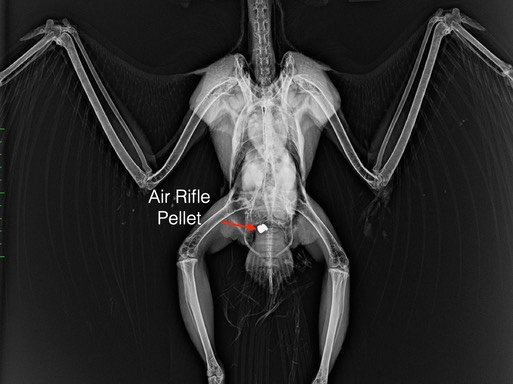

It wasn’t all baby birds this week. Sadly, this adult Swainson’s Hawk was shot near Athena. He had no feeling in his feet or use of his legs and was euthanized. The air rifle pellet that caused the damage is visible on the radiograph below.